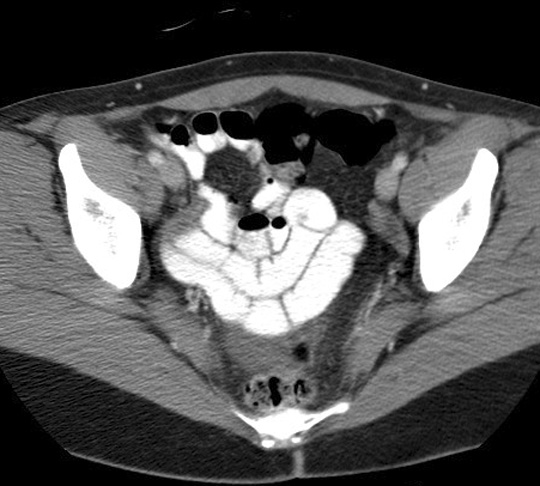

Where is the ileum usually located? Click the image for labeling.